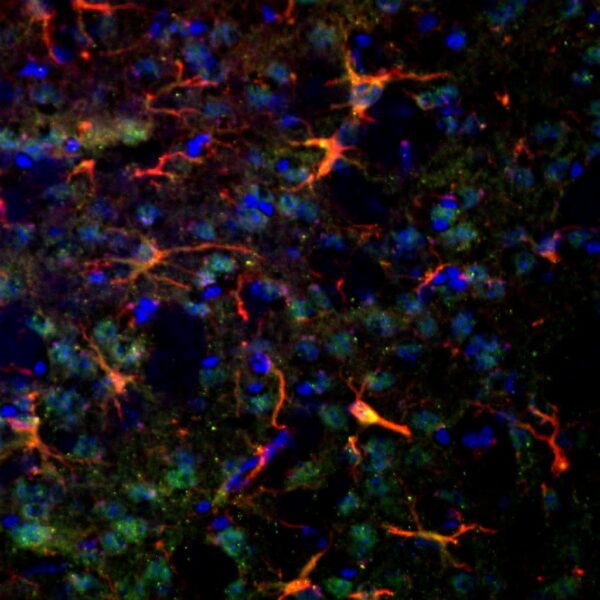

Astrocytes, Recycling, and the Brain-Derived Neurotrophic Factor

What can quantum dot technology reveal about how astrocytes recycle?